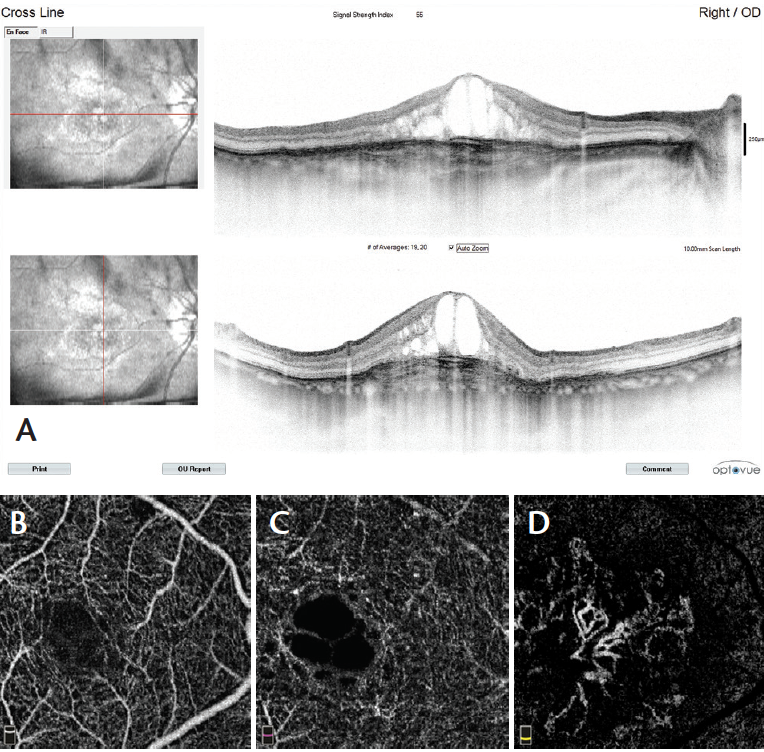

Figure 7. Typical AngioVue report in type 1 CNV. The cross-sectional OCT shows irregular subretinal fluid with thickened photoreceptor outer segments. Hyperreflective material is evident at the fluid site with irregular retinal pigment epithelium. OCTA shows normal texture of the vascular retina (superficial and deep capillary plexuses). A large, irregular neovascular network is evident in the choriocapillaris layer.

Figure 8. Cross-sectional OCT in type 2 CNV reveals CME, white intraretinal dots, and pseudostratified substance below the retina (A, right-hand images). OCTA scans show normal texture of the vascular retina in the superficial (B) and deep (C) capillary plexuses. The avascular zone (D)reveals a large neovascular wheel-shaped network with a central main mature vessel surrounded by growing loops.

In type 2 CNV (Figure 8) new vessels are always located above the retinal pigment epithelium, but they also spread deeply into the outer retinal avascular area. The flow is high; however, the morphology is less varied than in type 1 CNV, with the morphology most frequently appearing as bicycle wheel or fan-like shapes (Video 3). The neovascular network area is smaller than in type 1 CNV.

In type 1 CNV secondary to AMD (Figure 7), the new vessels initially appear under the pigment epithelium, and no flow is seen in the avascular outer retina. The neovascular network is often extensive, with high flow and varied morphology (Video 2). New vessels may appear in a variety of shapes, including a medusa head, coral reef, bicycle wheel, fan, and dead tree. The tangled network generally contains filaments, loops, and a vascular arcade. The vascular complex almost always has a feeder trunk or a bundle of feeder vessels.